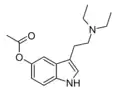

| 5-AcO-DET | artificial | 5-OCOCH3 | CH2CH3 | CH2CH3 | 5-acetoxy-N,N-diethyltryptamine | |